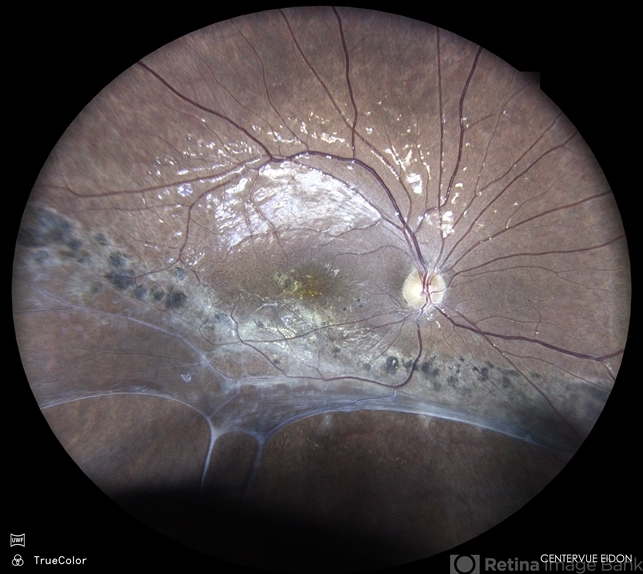

- RD, BARRAGE LASER

- Color fundus photograph of a 19 year old male with an inferior retinal detachment holding well years after prophylactic barrage laser in a one eyed patient.